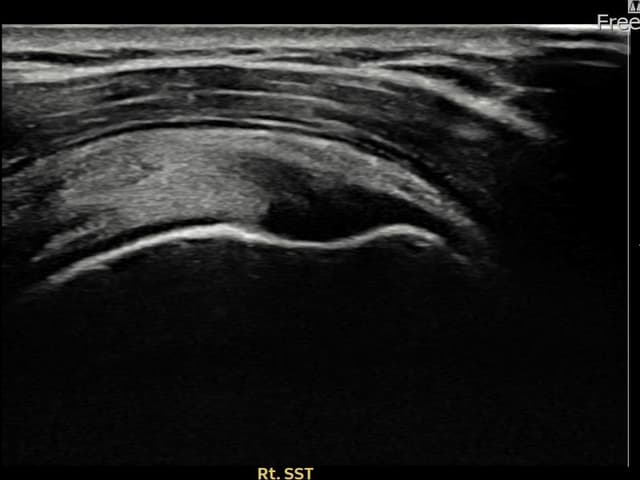

左侧 冈上肌腱 石灰化肌腱炎

9mm × 7mm